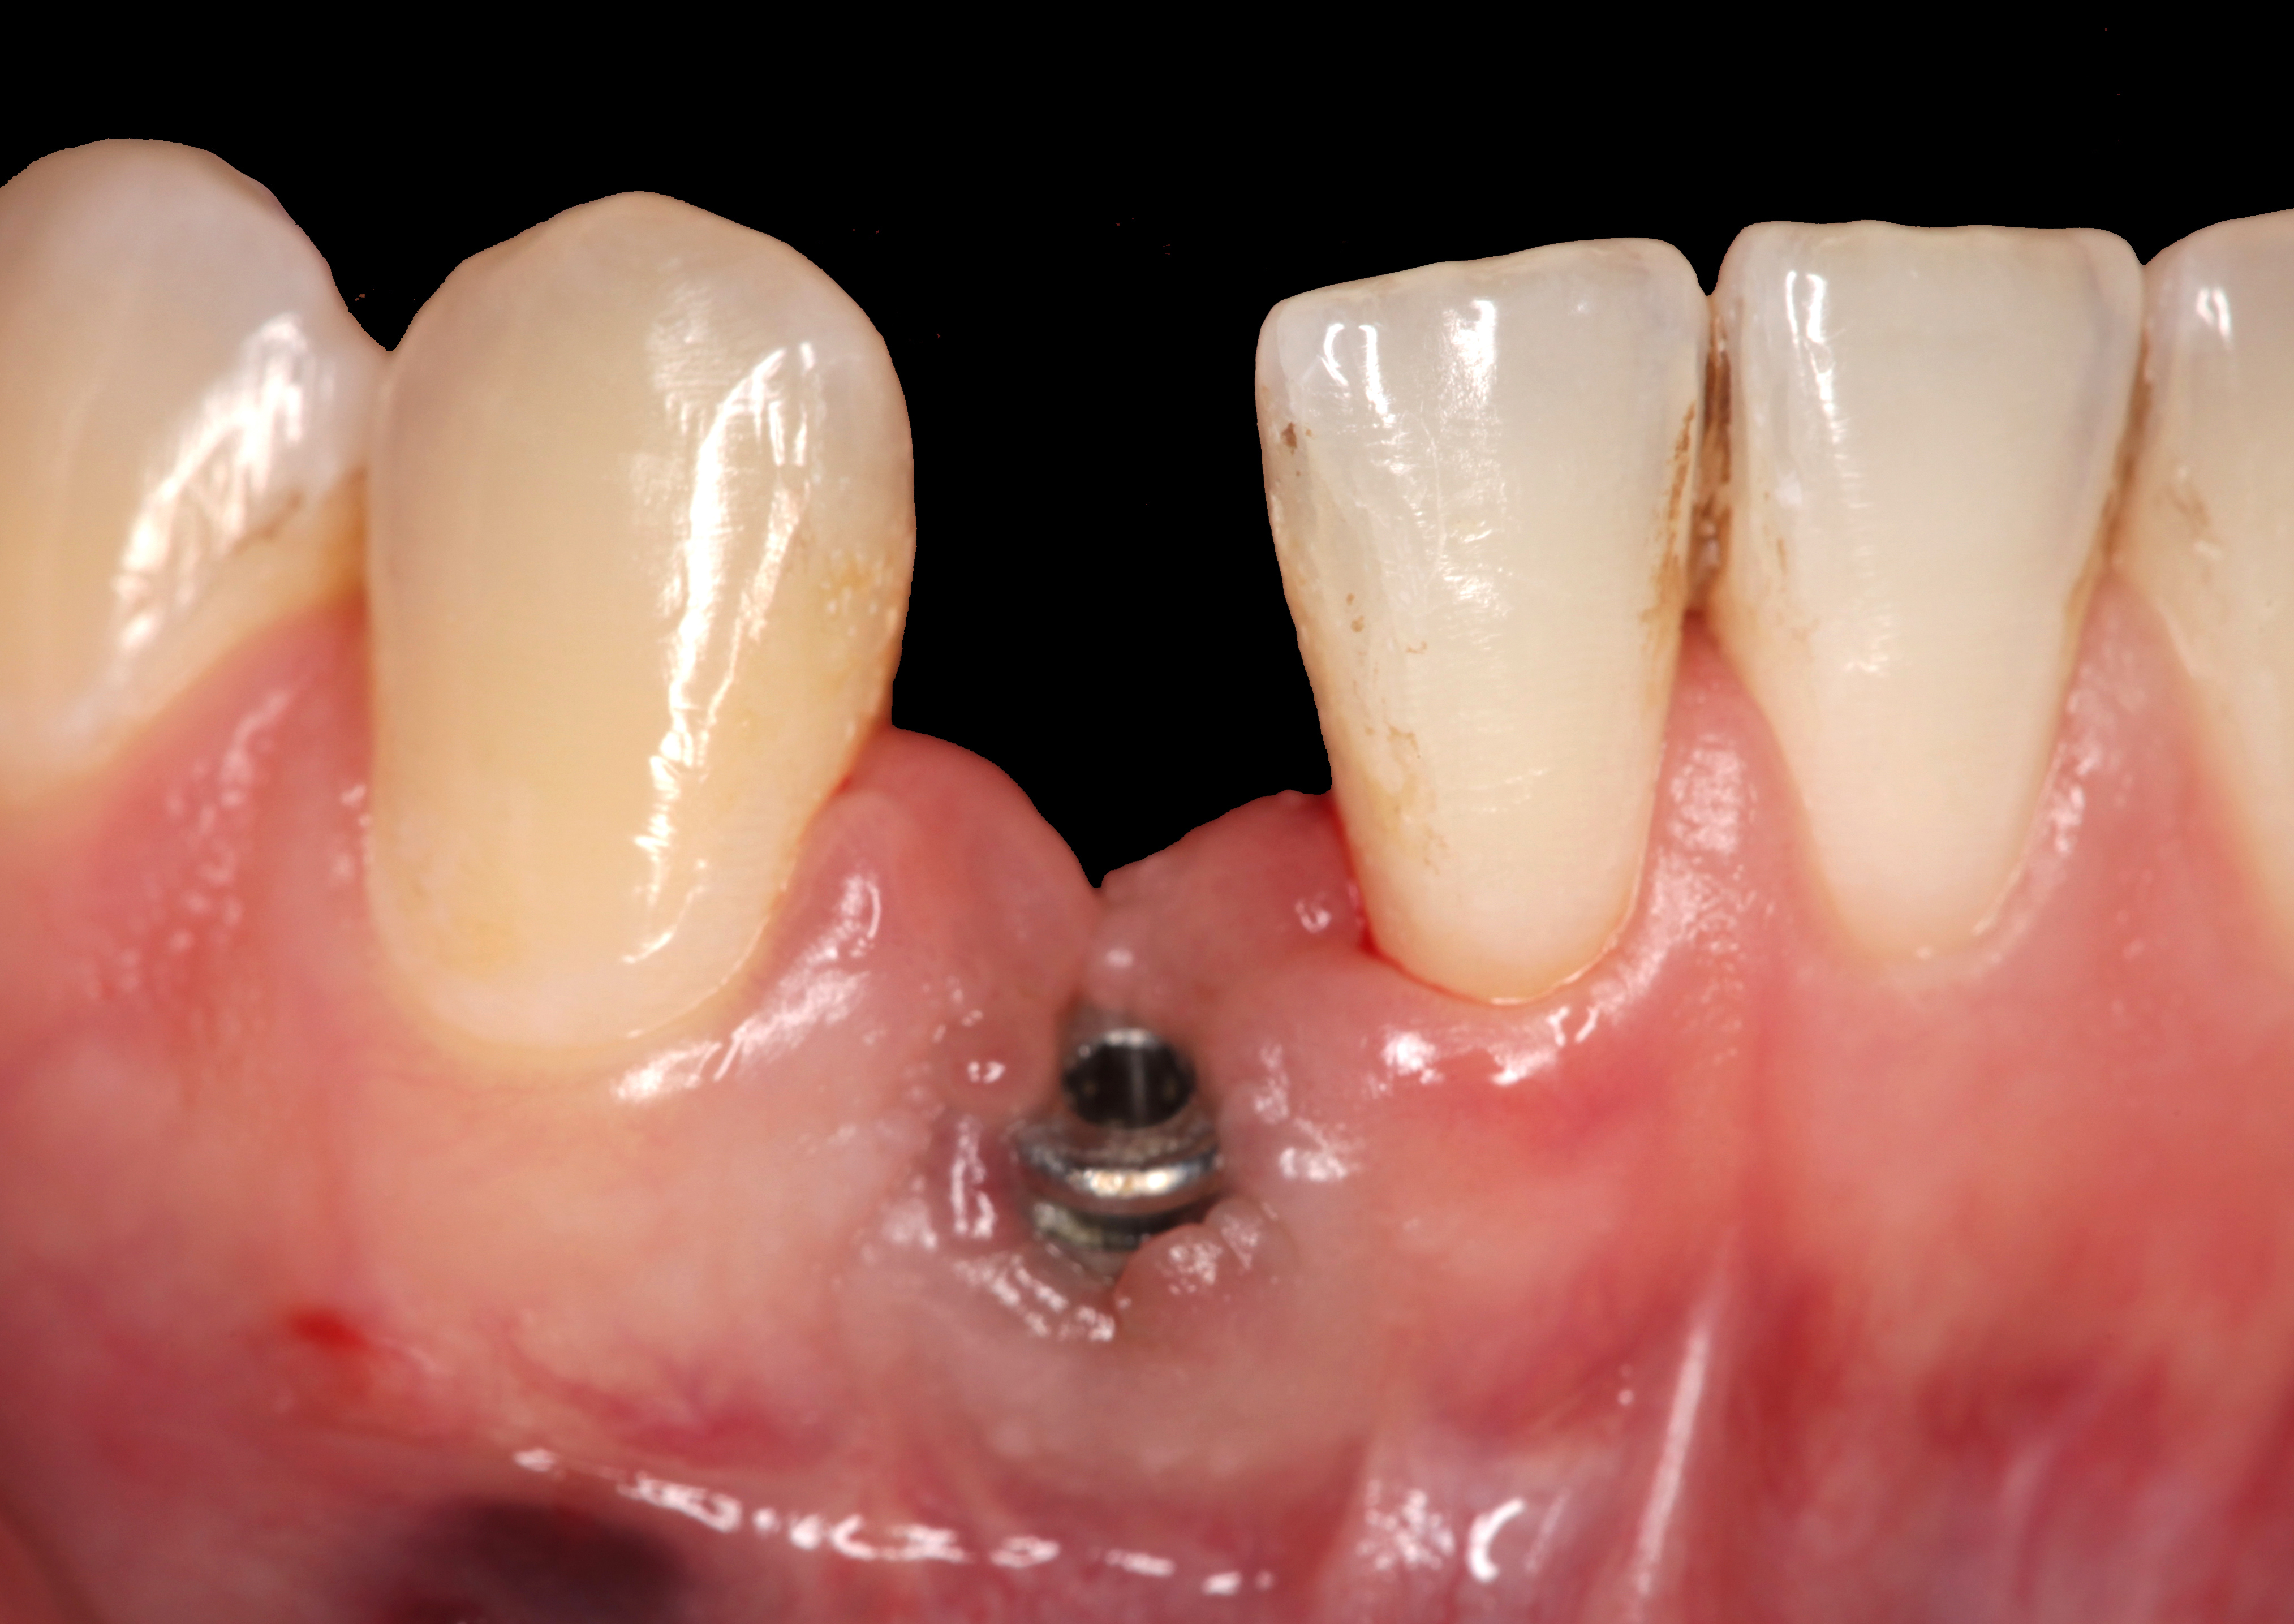

Fig 15. The implant-supported restoration of tooth No. 19 presented with a lack of attached keratinized gingiva, shallow buccal vestibule, and 2 mm of buccal recession.

Figure 15

Fig 16. The restoration exhibited an 8-mm pocket upon probing, with bleeding on the buccal aspect.

Figure 16

Clinical examination showed 2 mm of buccal recession with a shallow vestibule and absence of keratinized attached gingiva against the crown with 8 mm of circumferential pocketing accompanied by bleeding upon probing (Figure 15 and Figure 16). A periapical radiograph showed a symmetrical vertical osseous defect causing the loss of 50% of the bone around the implant (Figure 17). Because the patient had made a significant investment of time and finances to replace her lost tooth with the implant, she desired that the implant and restoration be retained, if feasible.